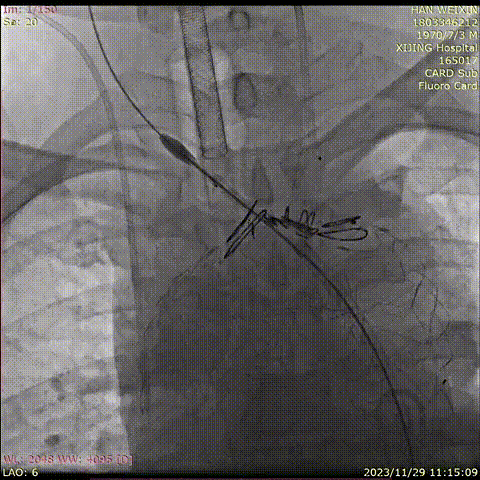

曹某,男,74岁,“胸背部疼痛10天”入院,主动脉CTA提示:主动脉弓可见多发穿透溃疡,较大之一径约1.2cm。高血压病史10年,血压最高190/80mmHg,糖尿病史12年。

术前CTA

术前

术后

手术用时80分钟